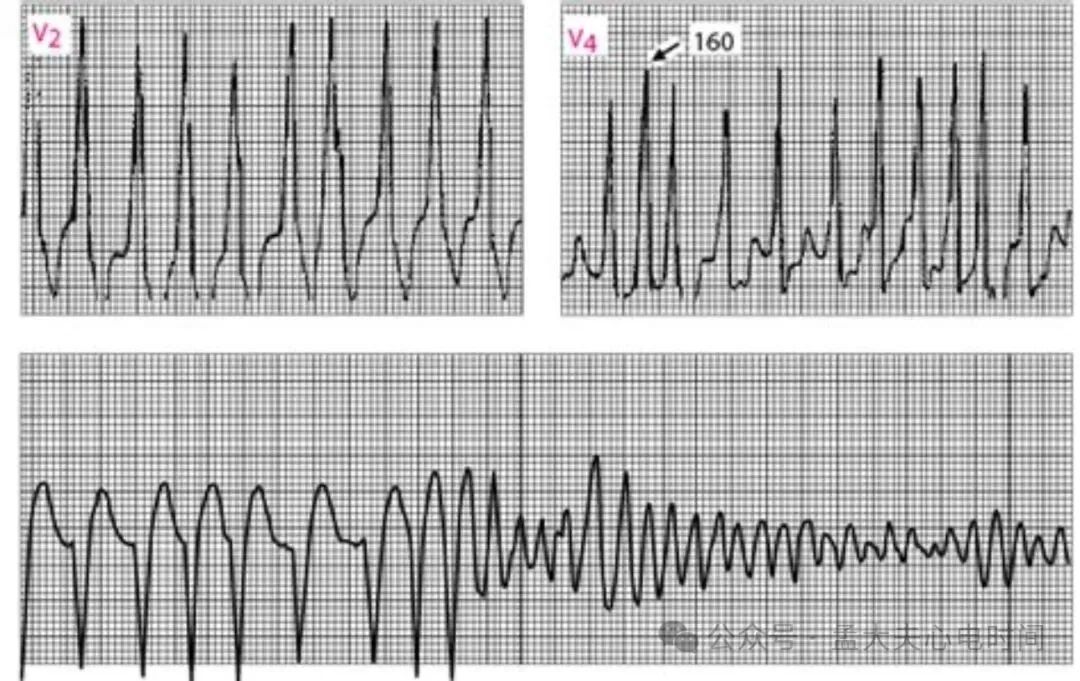

RR间期绝对不规则:心室率快且完全不整齐。

QRS波宽大畸形:宽度≥0.12秒,起始可见预激波(delta波)。

平均心室率>200bpm:旁道不应期短,传导速度快,最短RR间期可≤250ms。

QRS波形态多变:宽窄交替(旁道与房室结交替下传形成融合波),逐跳形态差异显著。

旁道不应期<250ms:极快心室率易诱发室颤。